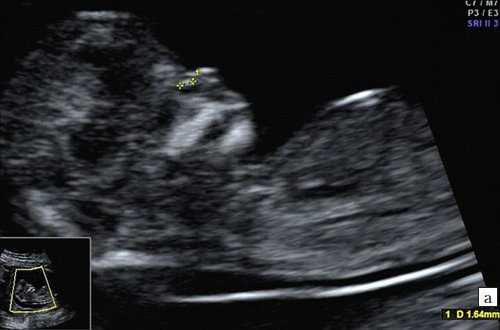

Считается, что носовая кость нормальна, когда она по своей структуре более эхогенна, чем надлежащая кожа и патологична, если она не видна (аплазия) (рис. 2) или ее длина меньше нормы (гипоплазия) (рис. 3). В случае одинаковой или меньшей эхогенности носовой кости чем кожи носовая кость считается патологической (рис. 4).

Рис. 4. Сниженная эхогенность носовой кости.

Итак, патологией носовой кости считается:

- изменение ее длины (гипоплазия);

- изменение ее эхогенности.